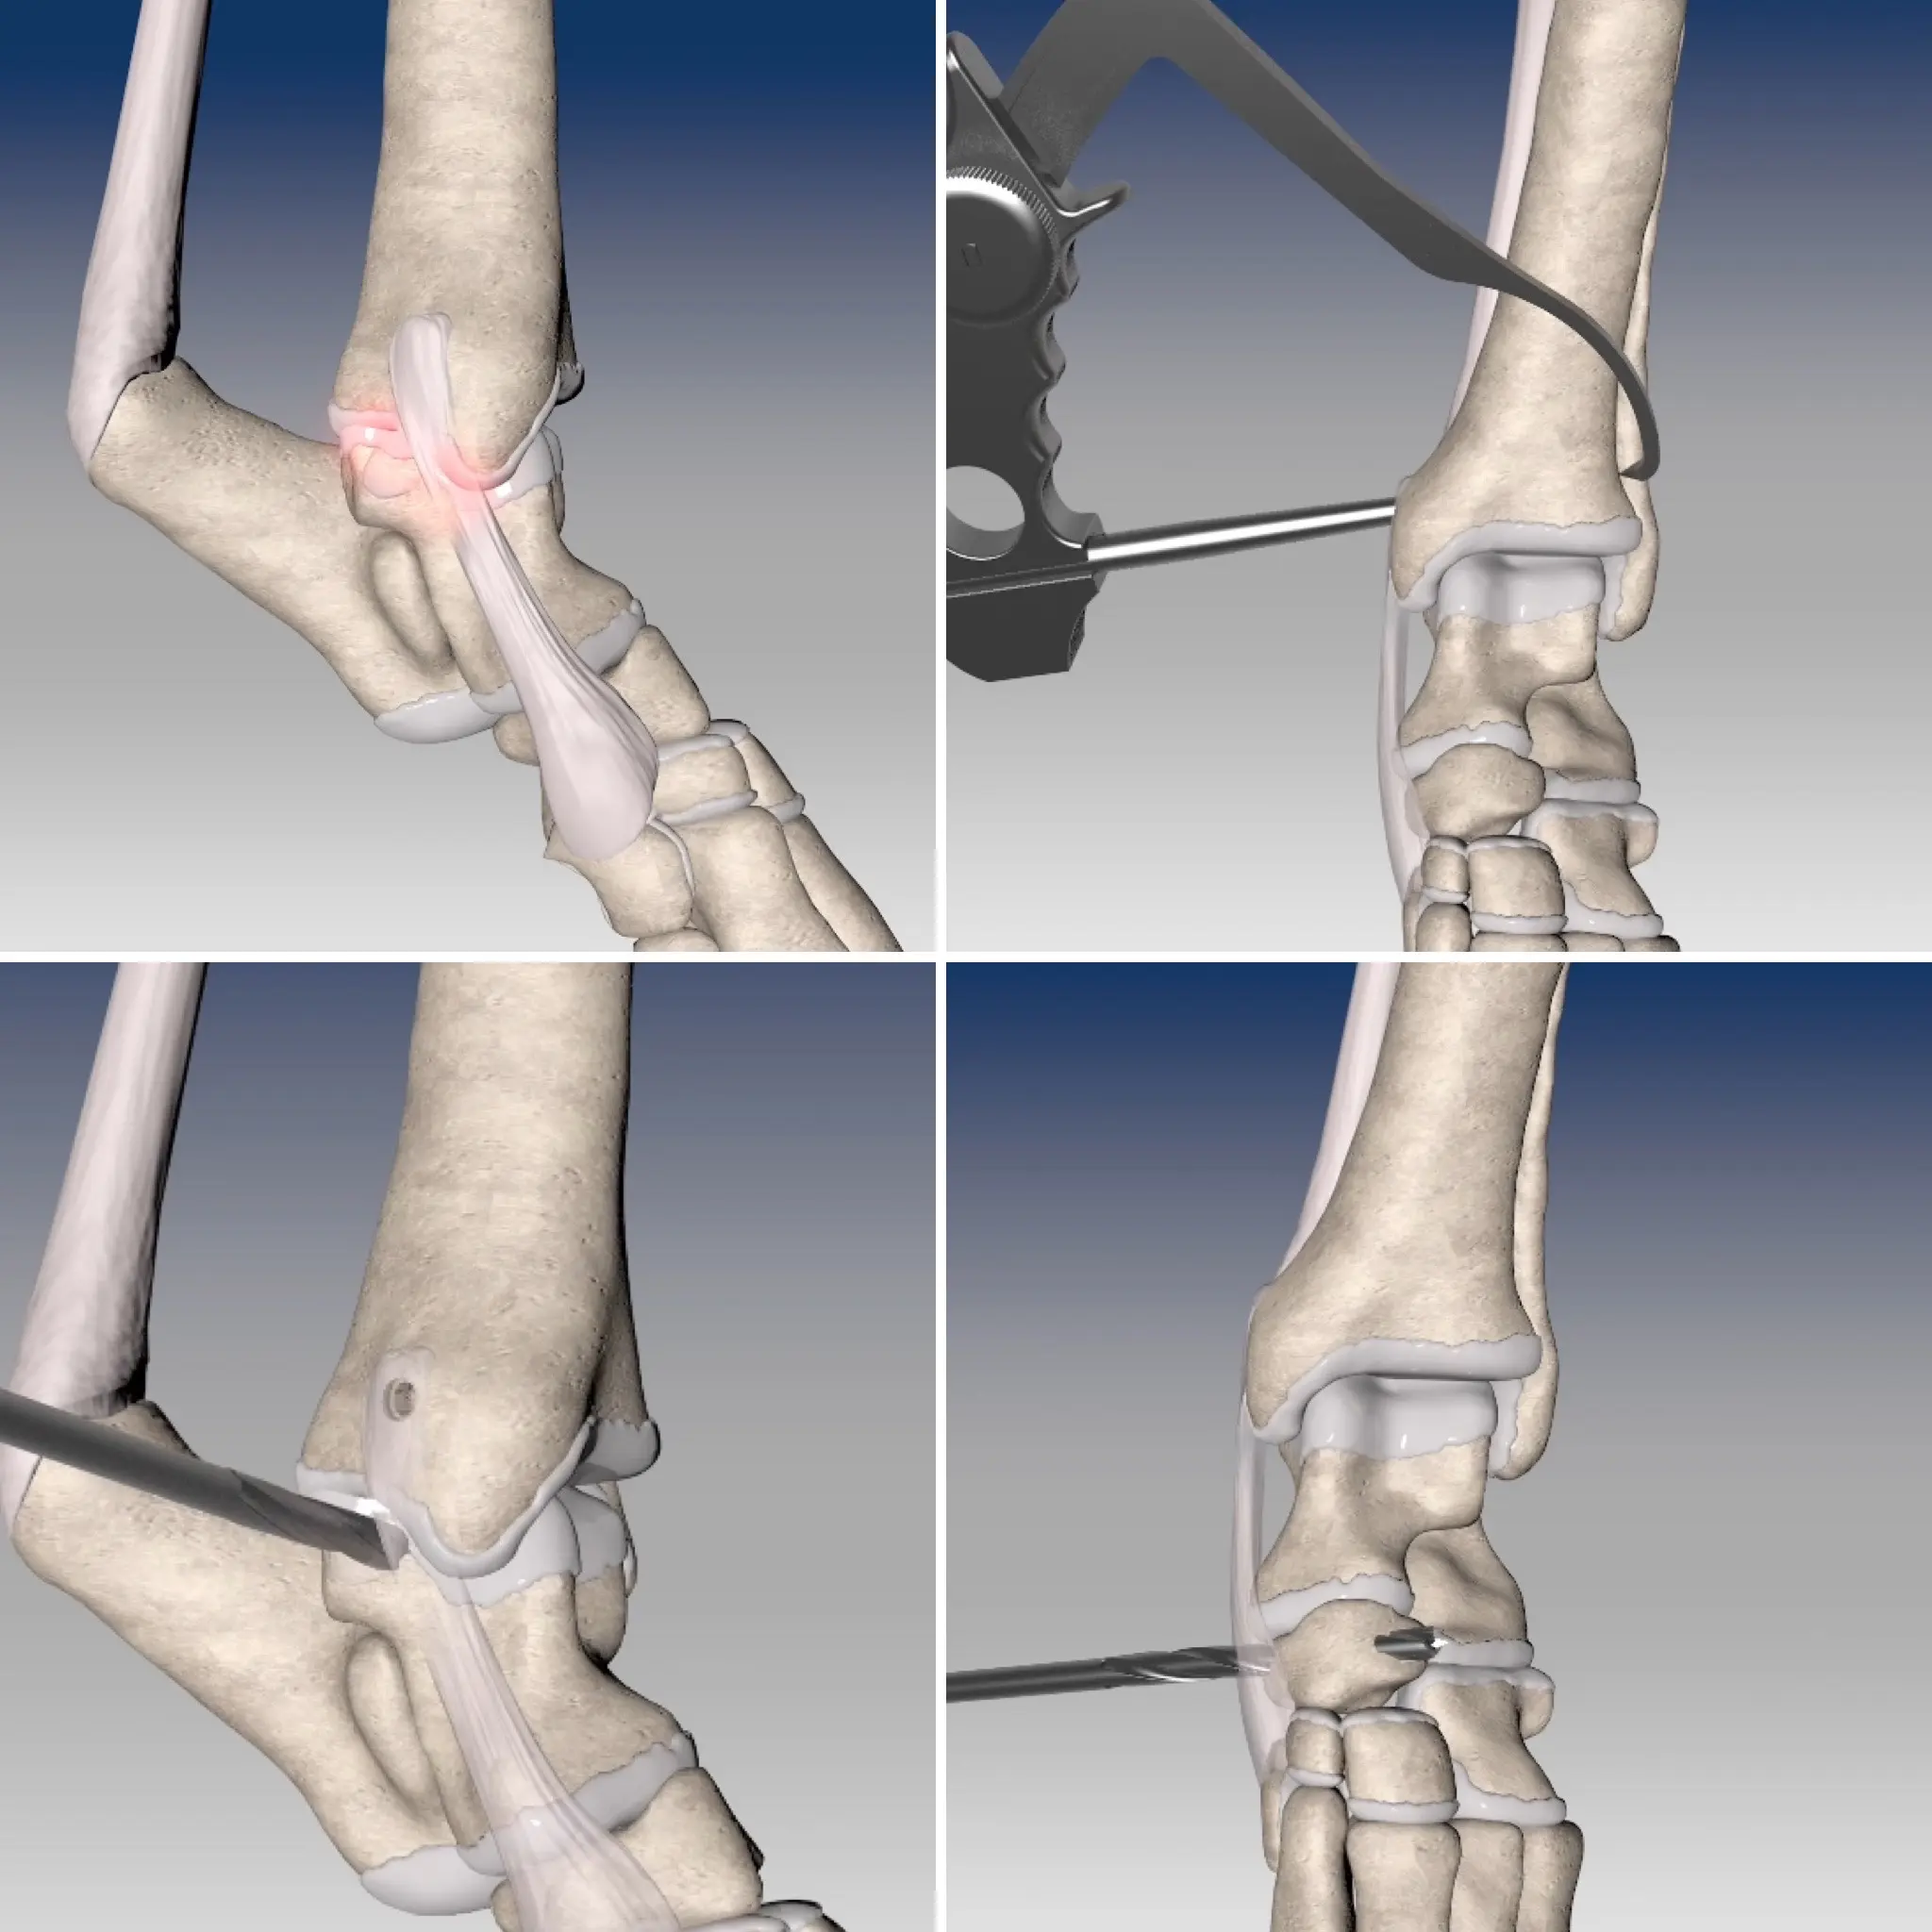

En esta ocasión esta fue la técnica empleada. El procedimiento consiste en primer lugar en crear unos túneles óseos en la región distal de la tibia, el astrágalo y el hueso central del tarso. Seguidamente a través de éstos túneles se hacen pasar los dos cabos del ligamento protésico, siendo fijados en su lugar de inserción mediante tornillos de interferencia. Gracias a ello conseguimos reconstruir completamente tanto la banda corta como larga del ligamento afectado, recuperando la estabilidad y función articular original.